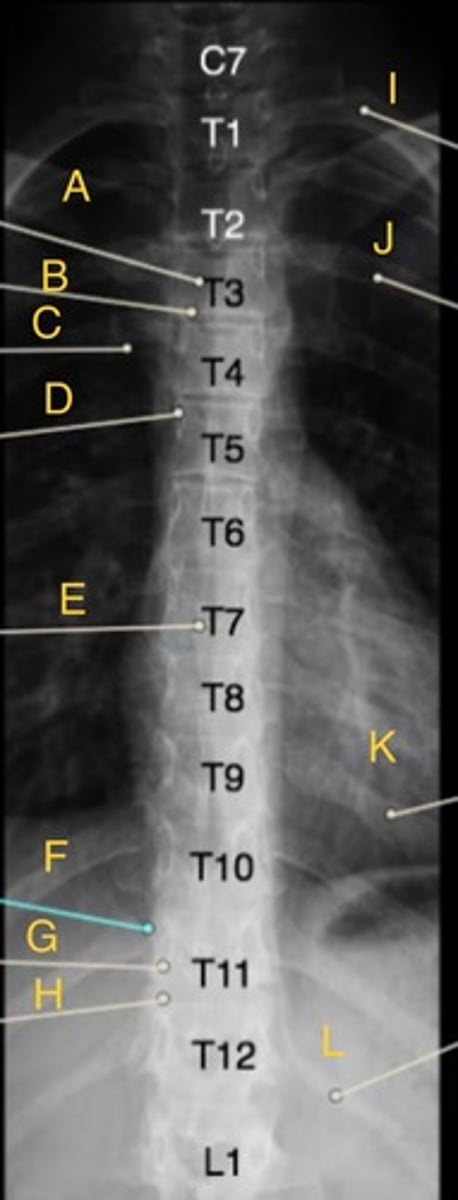

L 1st rib

I.

L 3rd posterior rib

J.

L 9th posterior rib

K

T3 body

A.

T12 floating rib

L

T3-4 intervertebral disk space

B.

T4 transverse process

C.

T5 Pedicle

D.

T7 spinous process

E.

T11 costovertebral joint

F.

T11 inferior articular process

G.

T12 superior articular process

H.

AP T-spine

What position?